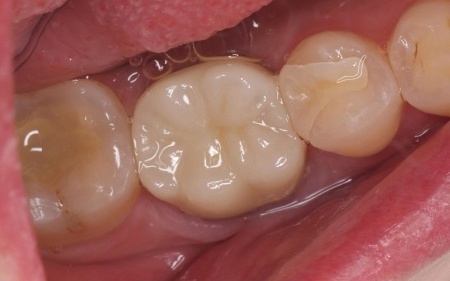

| 行ったご提案・治療内容 | 欠けた被せ物は10年以上前に治療した部位とのことで、材質はセラミックの一種であるポーセレンだと考えられます。 再び破折する危険性を考慮して、セラミックの中でも人工ダイヤモンドと呼ばれるほど高い強度をもつ「ジルコニア」での修復を提案し、同意いただきました。 メリット デメリット まずは右下奥歯の古い被せ物を除去し、歯の形を丁寧に整えます。 後日、完成した被せ物を装着し、見た目や噛み合わせに問題がないことを確認して、治療を終了しています。 |

治療後